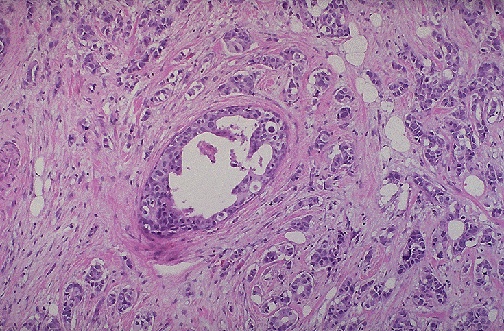

Image 2.3

Microscopically at medium power, the breast lesion is shown here.